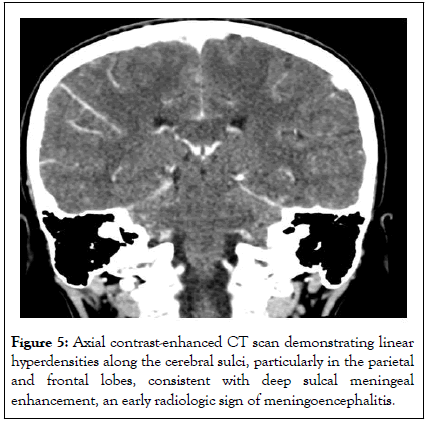

A 10-year-old girl presented with 10 days history of fever and gastrointestinal symptoms. Her condition didn’t improve despite a course of oral antibiotic treatment. On admission, the patient was febrile, restless, with neck stiffness. Inflammatory markers were within normal limits. A CSF sample showed neutrophilic pleocytosis, high protein levels and low glucose levels; cultures and PCR tests were negative (Tables 1-3). The brain CT scan with contrast revealed sulcal meningeal enhancement (Figure 5).

The result of Mycoplasma pneumoniae IgM was positive. IV levofloxacin was started instead of ceftriaxone, with resolution of fever within 48 hours. She received a 10-day course of treatment without neurological sequelae.

Figure 5: Axial contrast-enhanced CT scan demonstrating linear hyperdensities along the cerebral sulci, particularly in the parietal and frontal lobes, consistent with deep sulcal meningeal enhancement, an early radiologic sign of meningoencephalitis.